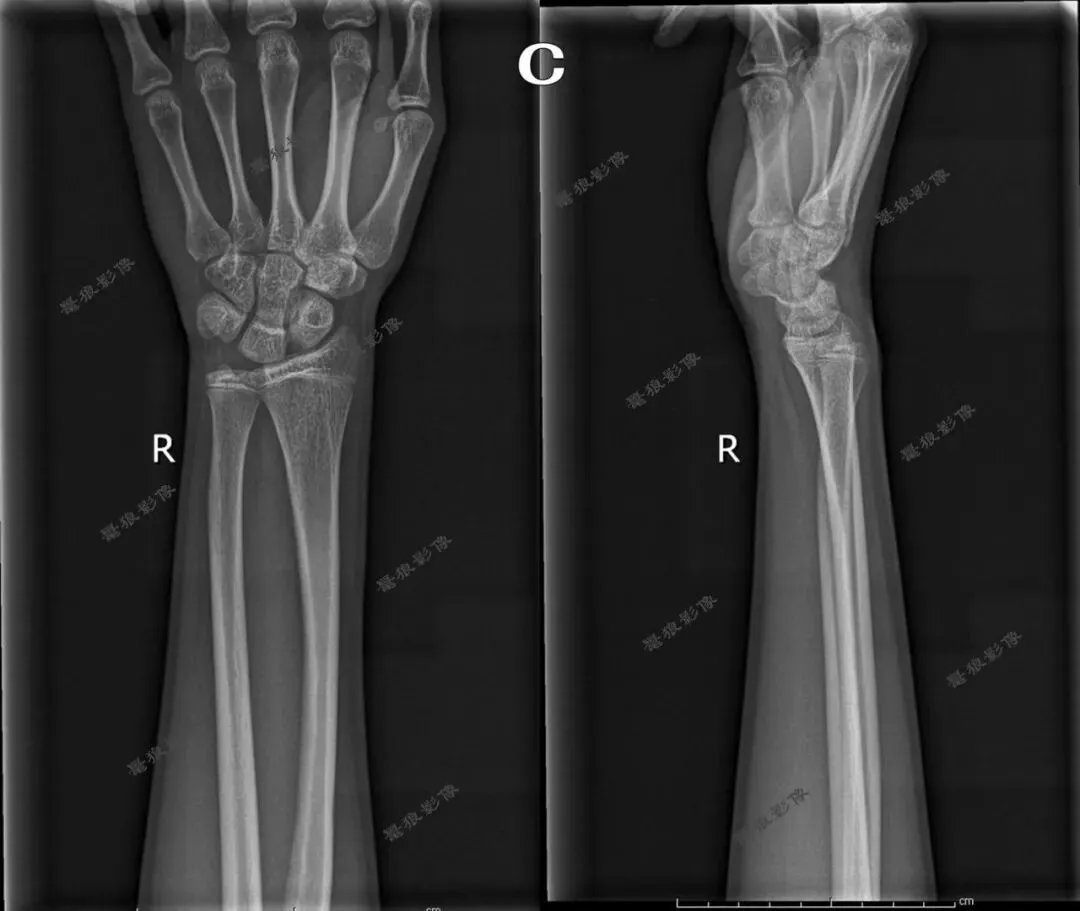

四、桡尺骨正位

1.摄影要点:

(1)受检者面向摄影台就坐,前臂伸直,掌心向上,背面贴近摄影台面,前臂长轴与探测器长轴平行;

(2)照射野和探测器上缘包括肘关节,下缘包括腕关节;

(3)源-像距离为100cm;

(4)中心线对准前臂中点,垂直射入探测器。

2.桡尺骨正位标准影像显示:

(1)显示桡、尺骨正位影像;

(2)腕关节和(或)肘关节呈正位像显示;

(3)诸骨纹理及周围软组织清晰可见。